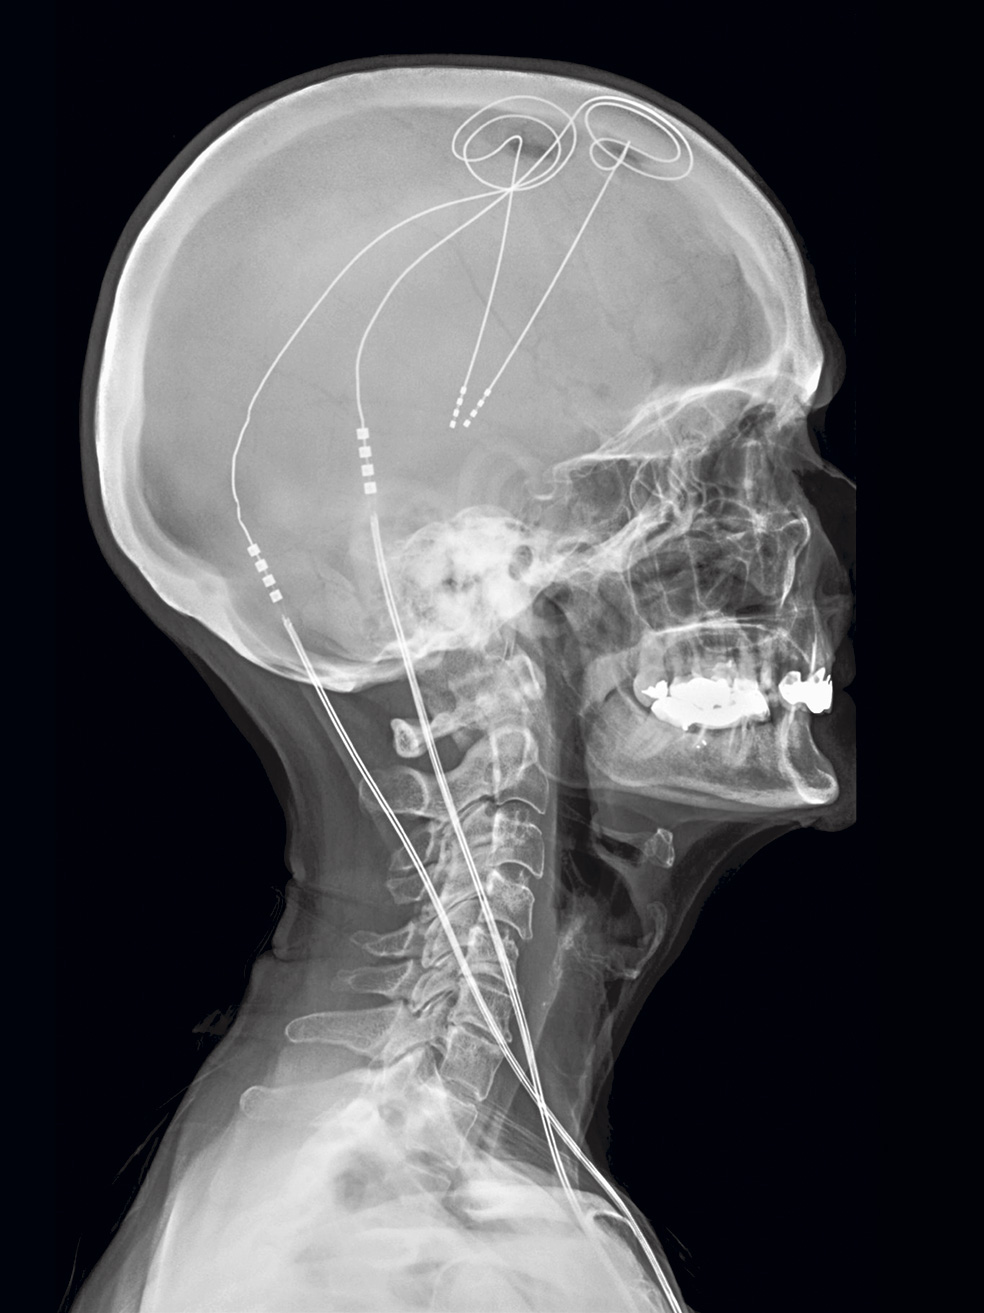

A la cabeza. Los electrodos usados en la estimulación cerebral, insertados en un paciente de forma permanente.

M.B. Con una intervención neuroquirúrgica se implantan una serie de electrodos en zonas muy precisas del cerebro para estimular su actividad. Ya se utilizaba, por ejemplo, para inhibir los temblores en enfermedades como el párkinson o la epilepsia resistente.

M.B. Los envía una especie de marcapasos que se coloca bajo la piel a la altura de la clavícula. Desde allí viajan a través de unos cables que van por detrás del cuello hacia el cerebro.